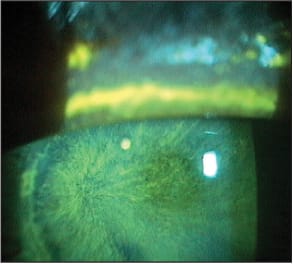

Note the pattern of corneal epithelial migration to fill in the braded area in this healing cornea.